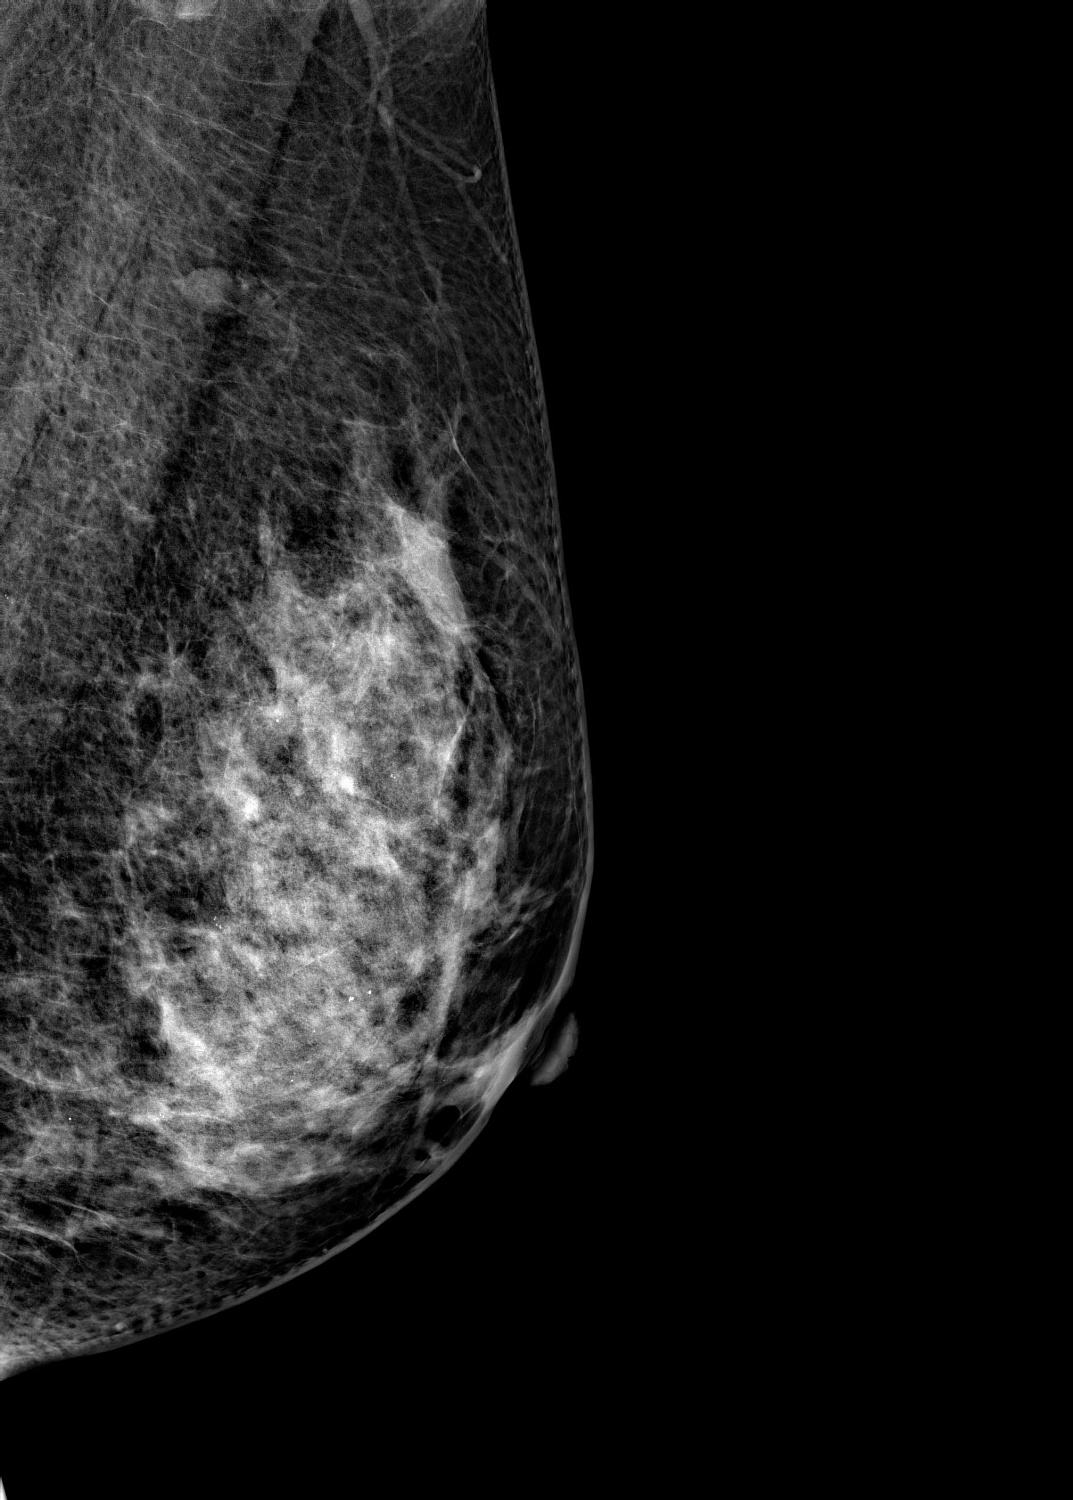

Маммограф выявляет опухоли молочной железы размером от 1-2 мм, которые не определяются при осмотре врача и самообследовании. На снимках хорошо различимы мельчайшие скопления солей кальция (от 87 мкм), тяжистые и другие перестройки тканей, характерные для рака груди 1-2 стадии. Высокую информативность, диагностическую ценность изображений обеспечивает цифровой детектор с самым чувствительным в мире сцинтиллятором. На снимках также определяются воспалительные процессы, кисты и даже небольшие повреждения.

Универсальный размер детектора делает обследование женщин с большим размером груди проще и безопаснее. Функция съемки молочных желез с имплантами позволяет обследовать эту категорию пациенток. На снимках хорошо различимы и ткани груди, и грудные эндопротезы.

Рентгеновский маммограф BRESTIGE EXPERT INDIRECT оснащен чувствительным сенсором непрямого преобразования на основе аморфного кремния. Цифровой детектор этого типа отличается надежностью и обеспечивает высокое качество изображения. Детальная «картинка» получается благодаря активной матрице, содержащей 2816 × 3584 пикселей, и хорошей квантовой эффективности (до 50%). На снимках ясно различимы даже небольшие изменения в структуре тканей и малоконтрастные образования.

Полноформатный детектор облегчает и ускоряет обследование женщин с большими молочными железами, а также делает его безопаснее. Пациенткам с грудью до пятого размера включительно для полноценного исследования достаточно 4 снимков: по 2 для каждой молочной железы. Аппараты, укомплектованные детектором меньшего размера, требуют 8 экспозиций.

Режим позволяет проводить маммографию у пациенток с грудными эндопротезами. На снимках хорошо видны ткани груди. Снимки отражают состояние импланта, в том числе его серьезные повреждения.